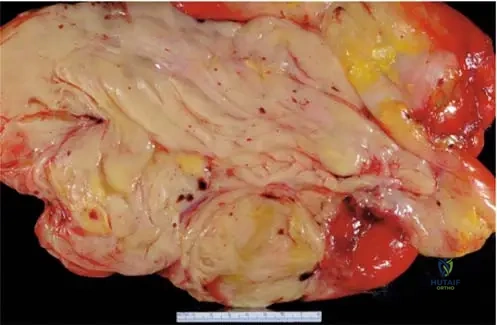

A 15-year-old female presents with a painful mass in her distal femur. A gross specimen of the resected tumor is shown. What is the primary characteristic that defines this tumor as an osteosarcoma?

View Answer & Explanation

Correct Answer: B

Rationale: Regardless of the gross appearance, the fundamental pathological definition of osteosarcoma is a malignant bone-forming tumor, meaning malignant cells producing osteoid. While gross specimens can show variability (e.g., blood-filled spaces in telangiectatic variants), the microscopic production of osteoid is the diagnostic hallmark. The image shows a destructive, heterogeneous mass consistent with a malignant bone tumor.